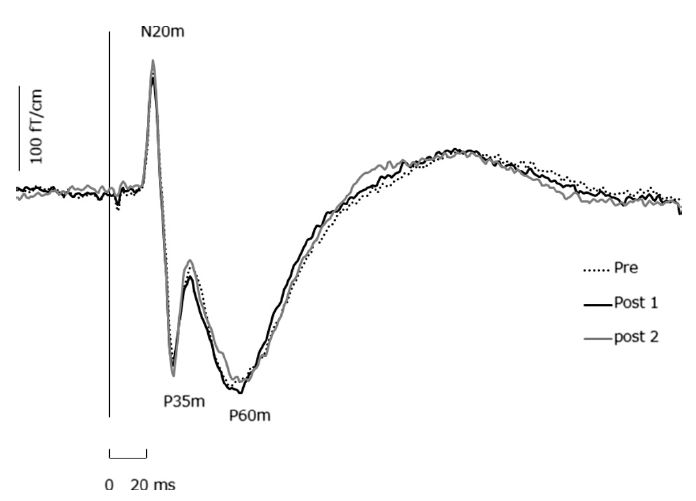

Sugawara K, Onishi H, Yamashiro K, Kojima S, Miyaguchi S, Kirimoto H, Tsubaki A, Tamaki H, Shirozu H, Kameyama S. The effect of anodal transcranial direct current stimulation over the primary motor or somatosensory cortices on somatosensory evoked magnetic fields.Clin Neurophysiol. 2014 (in press)

Onishi H, Sugawara K, Yamashiro K, Sato D, Suzuki M, Kirimoto H, Tamaki H, Murakami H, Kameyama S. Effect of the number of pins and inter-pin distance on somatosensory evoked magnetic fields following mechanical tactile stimulation. Brain Research, 2013, 1535:78-88

Onishi H, Oyama M, Soma T, Sugawara K, Kirimoto H, Murakami H, Kameyama S.(2011) Muscle-afferent projection to the sensorimotor cortex after voluntary movement and motor-point stimulation: An MEG study. Clinical Neurophysiology. 122: 605-610